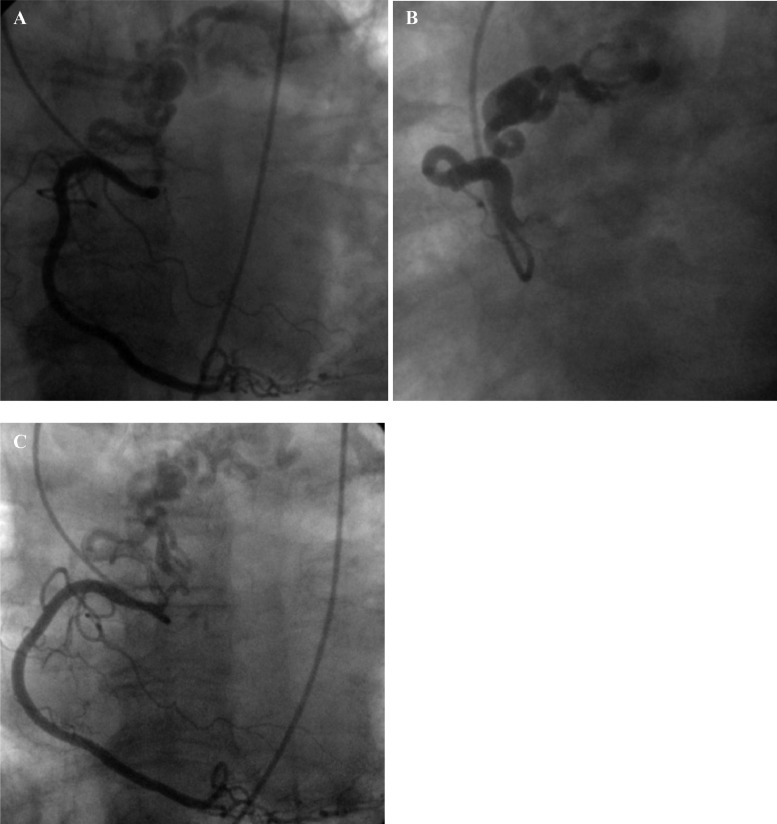

Fig. 1.

CXA of the left coronary-to-pulmonary artery fistula with saccular aneurysm.

CXA showed coronary-to-pulmonary artery fistula arising from proximal tract of left anterior descending artery with a giant saccular aneurysm in latero-lateral (A–B) and in antero-posterior (C) projections.

Fig. 2.

CXA of right coronary-to-pulmonary artery fistula.

CXA showed coronary-to-pulmonary artery fistula arising from a branch of RCA in latero-lateral (A–B) and in antero-posterior (C) projections.